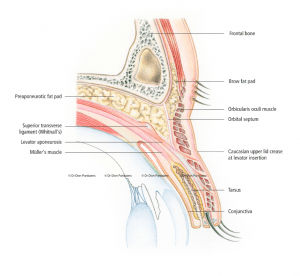

It is important that the doctor performing this procedure has special expertise in this area. Oculoplastic surgeons are ophthalmologists who specialize in eyelid surgery and who – like no other – understand the complex relationship between the eye and the eyelid. For example, an assessment of the different aspects of the eyelid such as eyelid height (the position of the lash line relative to the pupil), the amount of skin, the presence or absence of a so-called eyelid crease (the line above which the skin fold forms), the shape of the epicanthal fold, and the position and shape of the eyebrow should all be made preoperatively. It is also important to look for signs of dry (or wet) eyes, as this helps to prevent eye complaints after the procedure.